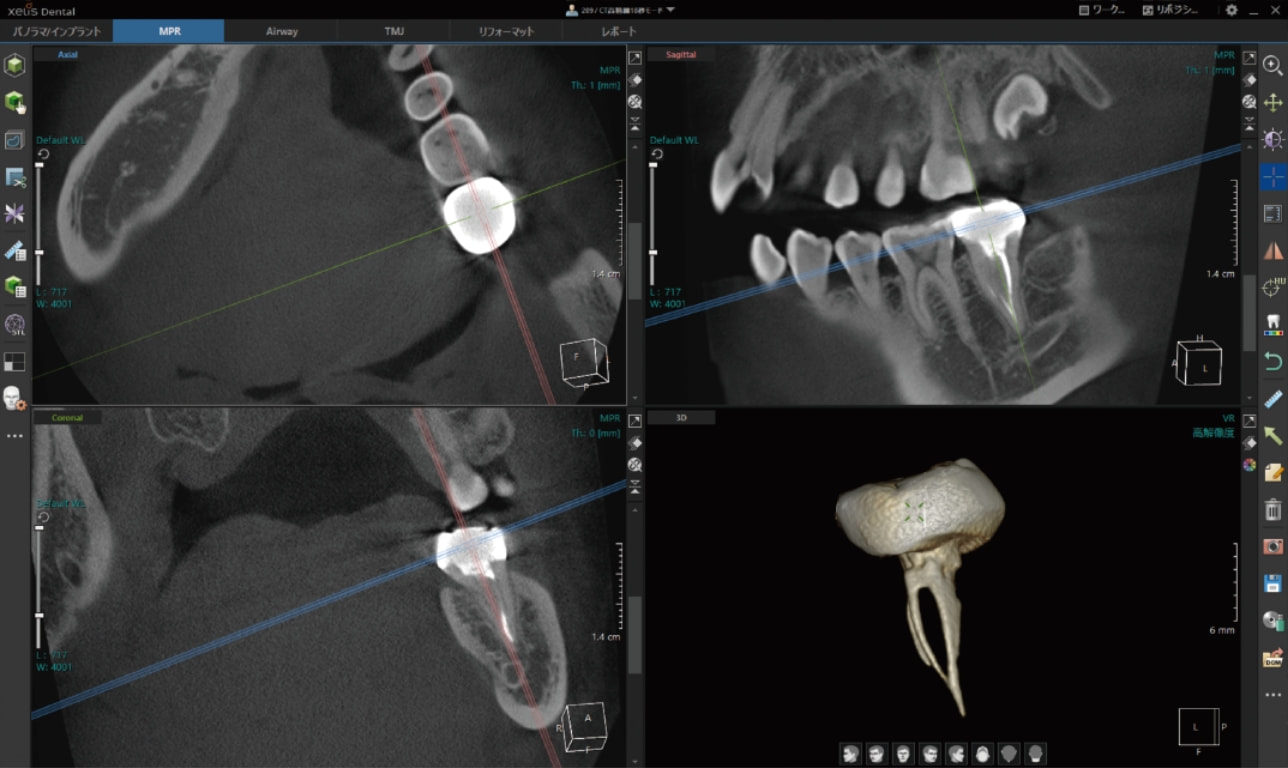

CT画像専用ビューアーソフト「 XelisDental(ゼリスデンタル )」

Pano/Implant、MPR、TMJの各種解析ツールをタブで切替できます。

タブの切替のみで、ツールアイコンが変化する為、迷わず操作が可能です。

VOI , Cube機能 / VRのスカルプト機能

MPR表示では、局所拡大表示も可能。

軸の回転に加え、スライス厚の変更やボリュームレンダリング画像のスカルプト機能も搭載。

VOIやCube機能で、解析部位を絞り込んで表示する事ができます。

歯科領域で必須とされる各解析ツールを搭載。